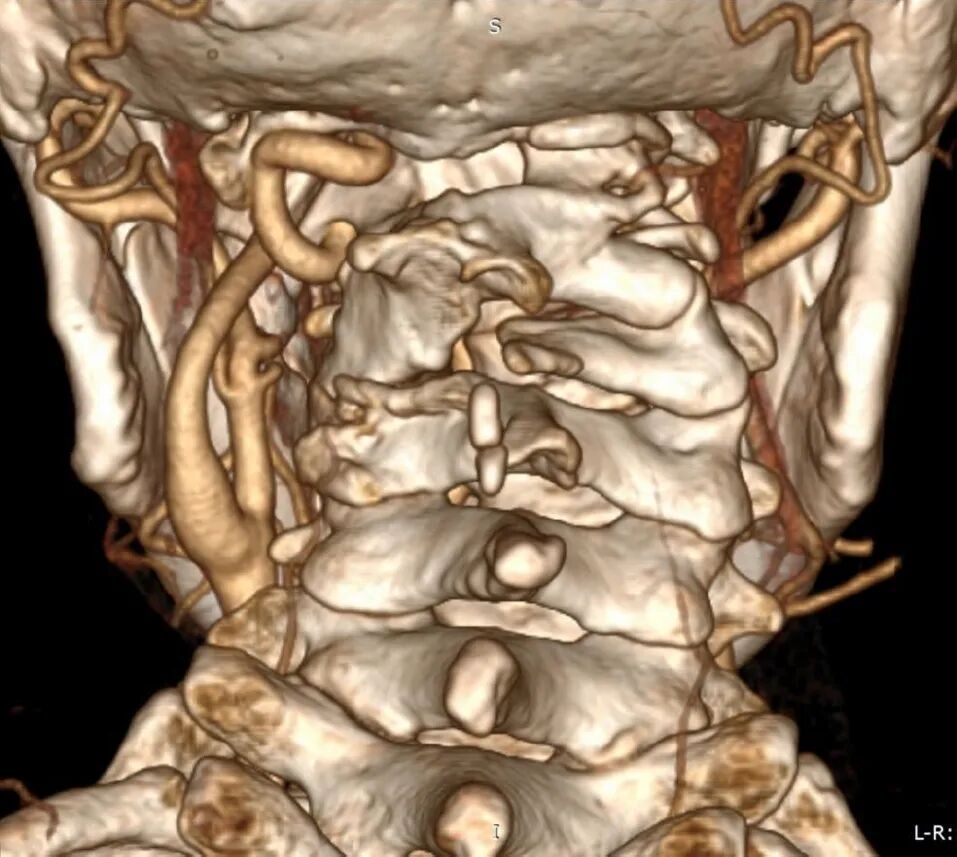

术前常规进行头颈部CTA扫描,应用计算机软件(推荐应用RadiAnt DICOM Viewer, Medixant Co.)对CTA Dicom数据进行三维重建详细观察颅颈交界区骨性结构畸形和椎动脉走行,制定手术方案,评估椎动脉损伤的风险。

椎动脉分型及手术策略

根据进行关节间操作时损伤椎动脉的危险程度,将椎动脉走行分为3种类型:低风险型,高风险型,禁忌型低风险型椎动脉:椎动脉走行不遮挡寰枢椎关节面,进行关节间操作损伤椎动脉的风险较低,此类患者通常没有寰枕融合,或寰枕融合不完全,寰椎保留横突孔结构,椎动脉受到寰椎横突孔的引导,走行路径正常,没有遮挡寰枢椎关节面(图9)。

对于此类椎动脉走行的患者,可以安全实施关节间撑开融合操作,手术中损伤椎动脉的风险较低。

高风险型椎动脉:椎动脉走行遮挡寰枢椎关节面,在进行寰枢椎关节间撑开操作过程中,损伤椎动脉的风险较高。并进一步分为Ⅰ型、Ⅱ型和Ⅲ型危险型椎动脉。

Ⅰ型高风险型椎动脉指患者一侧椎动脉走行异常,手术中损伤几率较高,但对侧椎动脉走行、管径正常,手术中损伤几率较低。手术中高风险椎动脉发生损伤,对侧低风险椎动脉可以代偿基底动脉血运,患者发生后循环缺血的风险较低(图10)。

Ⅱ型高风险型椎动脉,指两侧椎动脉皆为高风险型椎动脉,由于两侧椎动脉均走行异常,因此术中均存在较高损伤风险,如两侧椎动脉同时被损伤,患者可能发生后循环缺血(图11)。

Ⅲ型高风险型椎动脉,指患者一侧椎动脉为高风险性椎动脉,而对侧椎动脉退化或缺如,一旦高风险型椎动脉损伤,对侧椎动脉无法代偿基底动脉血供,可引发致命性基底动脉缺血(图12)

对于高风险型椎动脉,我们采用的治疗策略是将椎动脉向头侧抬起。显露寰枢椎关节后缘后,将关节间撑开器完全插入关节,如此,在旋转撑开器对关节间隙进行撑开的过程中,与椎动脉接触的是撑开器柱状的连接杆,避免对椎动脉造成卡压和切割,降低椎动脉损伤的风险(图13)。

禁忌型椎动脉:椎动脉穿行于寰枢椎关节面,进行寰枢椎关节间操作必然损伤椎动脉(图14)。这种椎动脉走行方式在关节间操作过程中尚无有效办法避开,因此是关节间撑开操作的禁忌证。